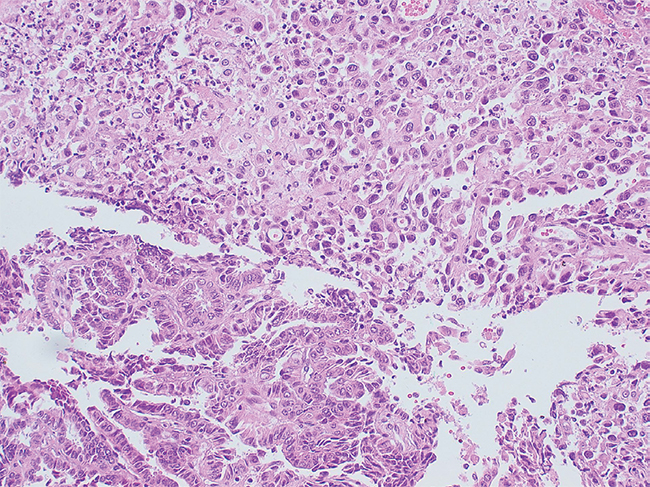

La biopsia concluye carcinoma papilar con desdiferenciación anaplásica (Figura 3), infiltrante en piel y tejidos blandos, con compromiso de márgenes quirúrgicos. Linfonodo de 12 mm con macrometástasis de carcinoma papilar.

Figura 3. Corte histológico con zonas correspondientes a cáncer anaplásico de tiroides y carcinoma papilar de tiroides en la misma muestra.Discusión